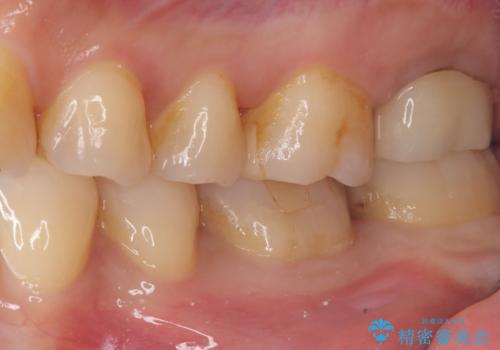

- 主訴:強く噛んだら歯がポロポロ欠けてきた。

左下6番目の歯の咬合面にプラスチックの材料が詰まっており、歯質がドーナツ状にしか残っていなかったため、歯質幅が比較的薄かった場所が欠けてしまったようでした。

今後の破折リスクを説明し、セラミッククラウンでのやり替えとなりました。

頬舌的レジンインレーが入っており、歯質幅の薄かった且つ強く咬合していた遠心側歯質が欠けてしまっていました。また新しい窩洞のインレーを入れても、近心側歯質の破折のリスクは抱えたままになることから、クラウンでの修復をおすすめし審美性・適合性のよいセラミッククラウンでのやり替えとなりました。